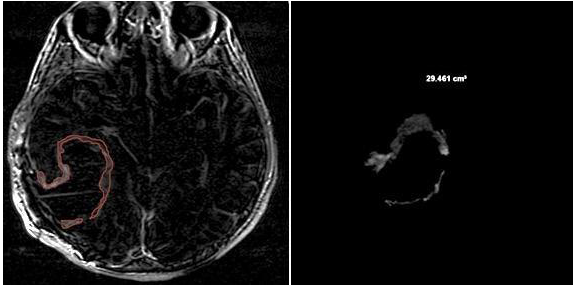

3.2. Quantitative Analysis

- CE-RTV: The median OS value was 19 months for patients with CE-RTV < 5.8 cm3 and 9 months for patients with CE-RTV > 5.8 cm3. The difference was statistically significant (p < 0.004) (Table 2).

- CE-RTV: The median PFS value was 5 months in patients with CE-RTV < 5.8 cm3 and 4 months in patients with CE-RTV > 5.8 cm3. The difference was statistically significant (p = 0.04).